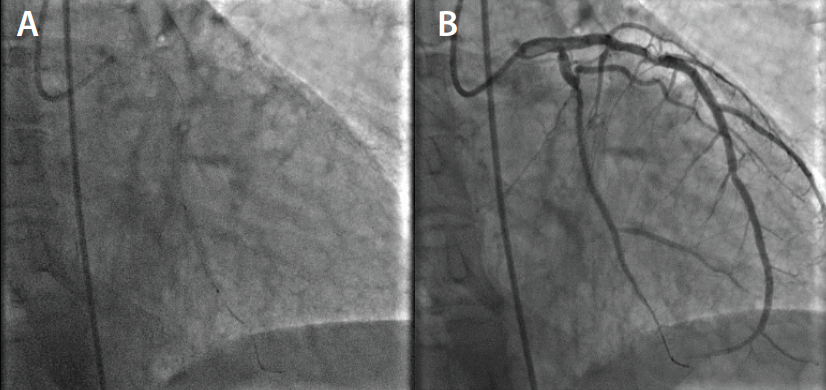

Left groin access was achieved under ultrasound guidance, and a 6-F vascular sheath was placed. Selective coronary angiography was performed in multiple views, revealing total in-stent restenosis in the mid–left circumflex artery (Figure 1). After imaging review, we decided to intervene on the lesion. Bivalirudin was started and 180 mg of ticagrelor was administered to the patient. A 3.5-F XB guide catheter was used to engage the LMCA. We were able to cross the chronic total occlusion initially using a Runthrough® guidewire (Terumo Interventional Systems). The wire was exchanged for an HT Pilot® 200 wire (Abbott Vascular) and a 0.014-inch support catheter (Figure 2). Sequential balloon angioplasty was performed from proximal to distal parts using a 1.5- X 6-mm Sprinter® OTW balloon (Medtronic), and then a 2- X 12-mm Mini Trek™ balloon (Abbott Vascular) was utilized (Figure 3). Laser coronary atherectomy was then successfully performed (Figure 4A). Postatherectomy coronary angiography revealed improved coronary blood flow (Figure 4B). Sequential balloon angioplasty was performed using a 2.5- X 20-mm Mini Trek™ balloon.

We then decided to place coronary stents. However, we had difficulty advancing the available stent even though the wire was changed to a stiffer wire and multiple techniques were attempted to no avail. We then tried a 2.5- X 24-mm EluNIR™ stent, and were able to successfully deploy the stent at the target lesion easily without any difficulty (Figure 5). We went on to deploy two more 3- X 24-mm EluNIR™ stents proximally, and finally, angioplasty with a 3.25- X 12-mm noncompliant Trek™ balloon was performed (Figures 6 and Figure 7A). Postprocedural coronary angiography demonstrated restoration of blood flow across the left circumflex artery with an excellent result (Figure 7B). At the end of the procedure, the patient left the cardiac catheterization lab stable and with no complications. The patient is discharged the next day.